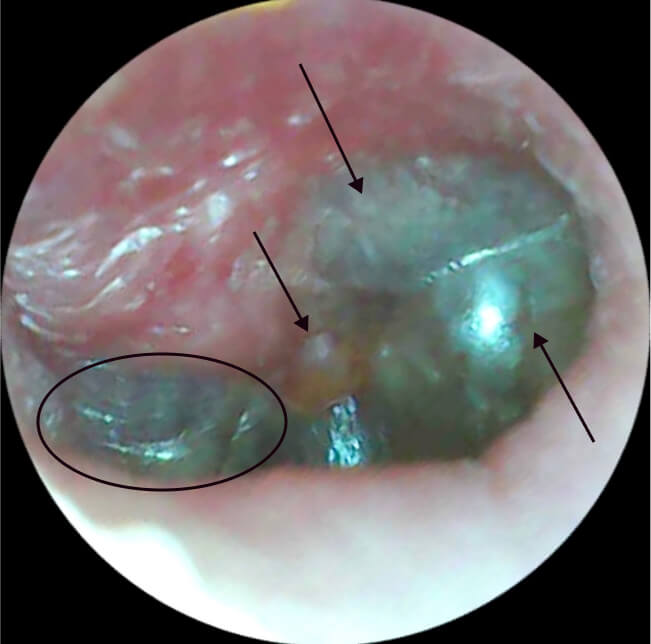

Хамар, хамрын дайвар хөндийн үрэвслийн үед явагддаг үрэвслийн процесс нь (түүнчлэн харшлын үед), цаг тухайд нь эмчилгээ хийгдэхгүй байвал чихний дунд, гадна ба дотор үрэвсэж, улмаар дунд чихний үрэвсэл үүсэхэд нөлөөлдөг байна. Ийм гэмтлийн үед өвчтөнд өвдөлт мэдрэн зовуурилах болно. Сүүлийн үеийн судалгаагаар, харшлын ринит нь хүүхдэд дунд чихний үрэвсэл үүсэхэд нөлөөлдөг хүчин зүйл болдгийг тогтоосон.

Энд та цоорлын өмнөх шатан дахь баруун талын цочмог явцтай дунд чихний идээт үрэвслийн эмнэл зүйн зураглал харж байна. Үзлэгээр чихний хэнгэргэн хальс нь хавагнасан, дээд хэсгээрээ хавдаж улайсан, голдуу арын доод квадрант хөөж хавагнасан, хэнгэргийн ард идээт шингэн хуримтлагдсан нь тодорхой харагдаж байна.